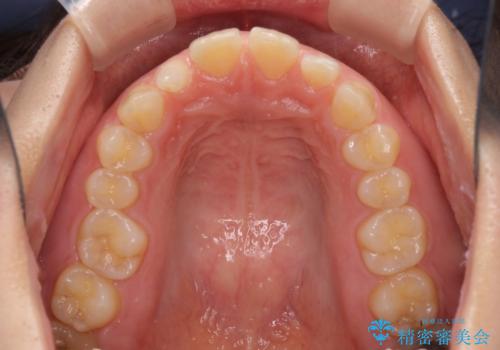

前歯の歯並びと小さい歯を改善 インビザラインとオールセラミッククラウン

- 前歯の空隙と矮小歯を気にして来院された患者様です。

上下の歯列不正はインビザラインにより整えることとしました。

矯正治療の後に、前歯1歯と奥歯をオールセラミックにて治療することとしました。

矯正治療により矮小歯前後にスペースを作りながら歯列を整え、セラミッククラウン装着後に最終的に歯列と咬合を仕上げました。